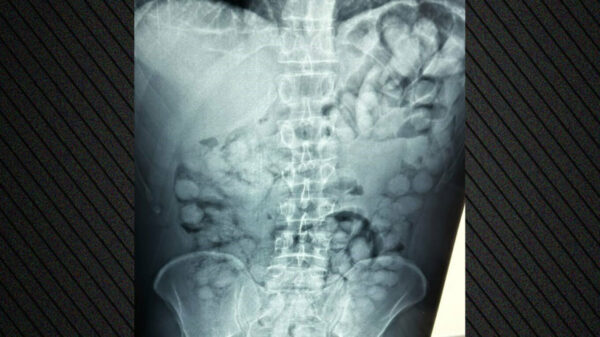

Συνελήφθη άνδρας στο Ελ. Βενιζέλος που είχε καταπιεί 100 συσκευασίες κοκαΐνης – Δείτε φωτογραφίες

Ο άνδρας από τη Βραζιλία έφτασε στην Αθήνα, μέσω Παρισιού